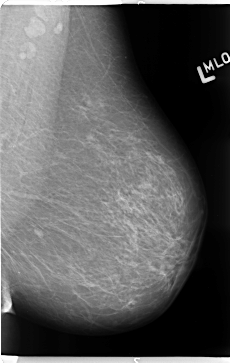

B_3113_1.LEFT_MLO

LEFT_MLO LINES 4712 PIXELS_PER_LINE 2984 BITS_PER_PIXEL 12 RESOLUTION 50 NON_OVERLAY